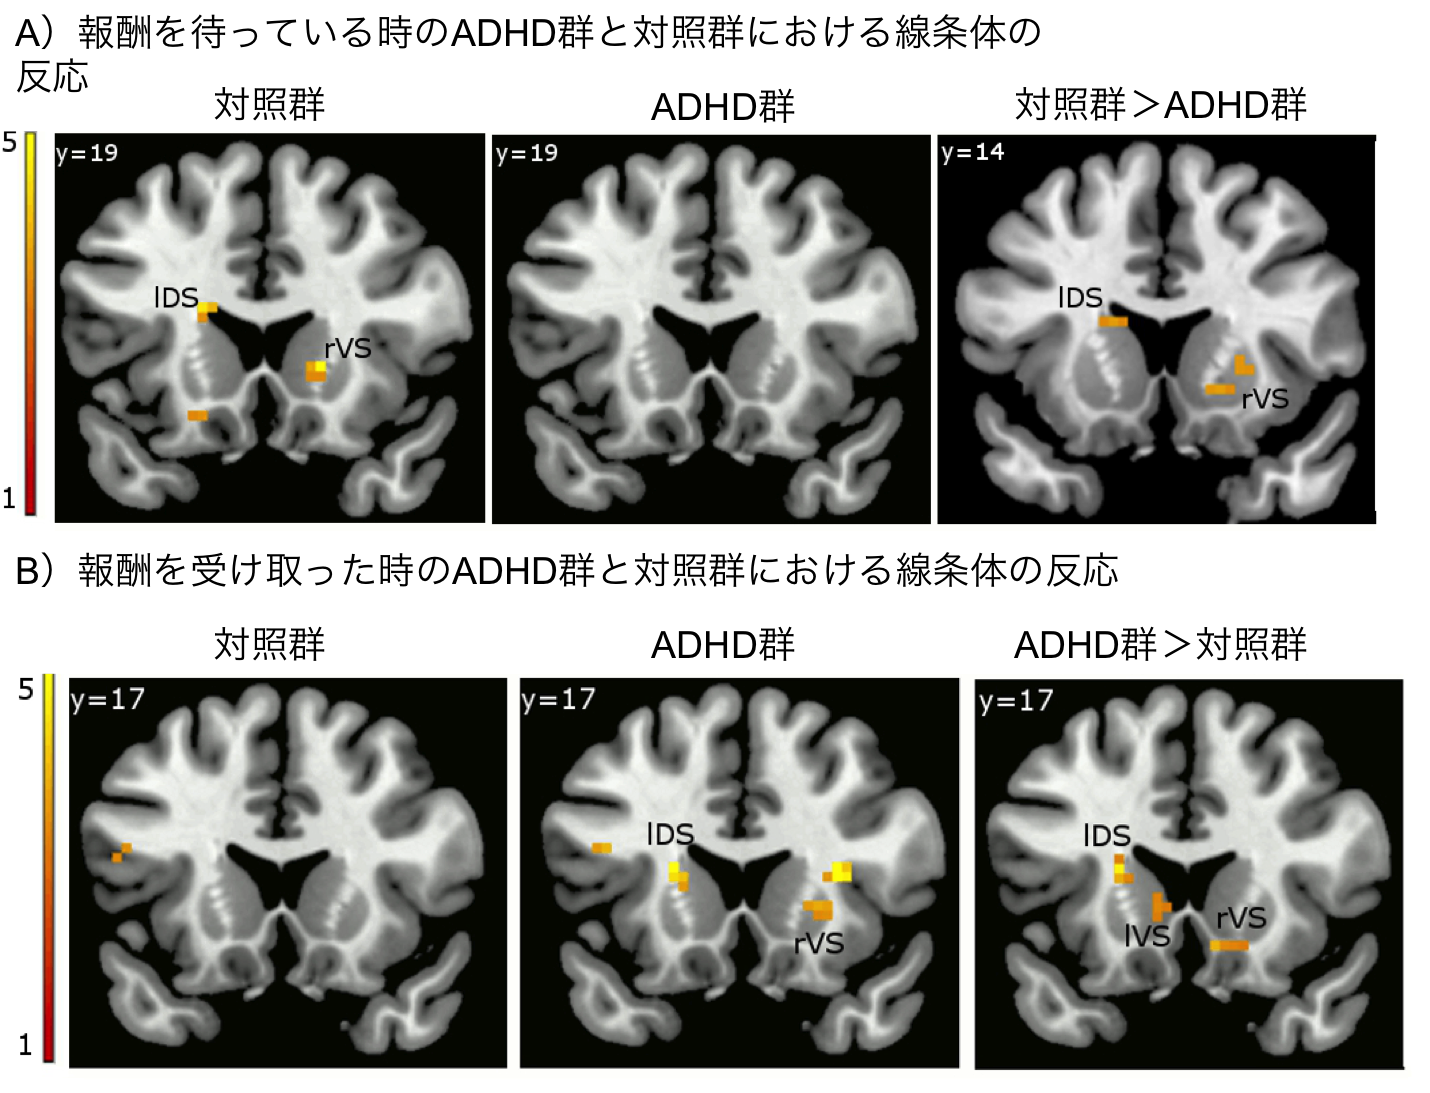

fMRI images showing differences in response to reward anticipation and delivery between adults with ADHD (ADHD group) and typically developing adults (control group). The color indicates the amount of activity, measured by changes in blood oxygen level, in the different areas of the brain.